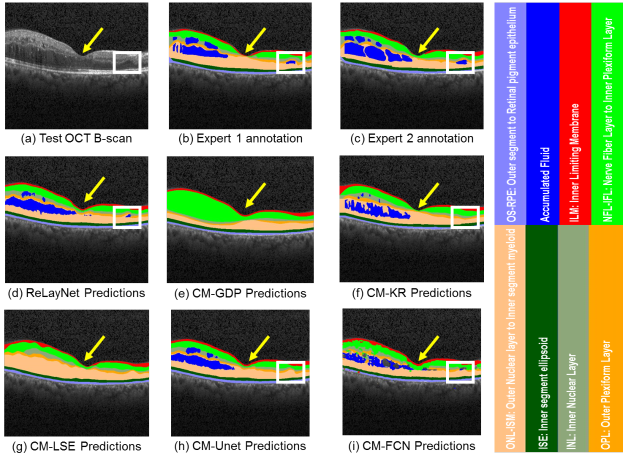

Refer to caption

Fig. 6: Layer and fluid predictions of a Test OCT B-scan near fovea with DME manifestation, shown in (a) with the expert 1 annotations in (b), expert 2 annotations in (c), ReLayNet predictions in (d) and predictions of the defined 5 comparative methods in (e-i). CM-GDP and CM-LSE doesn’t include predictions for fluid. The fovea is indicated by the yellow arrow. The region with a small fluid mass is shown by a small white box.

We present a qualitative comparison of ReLayNet in contrast with the comparative methods for two cases: an pathological OCT B-scan with DME (as shown in Figure 6) and for an OCT B-Scan sans fluid accumulation distal from the fovea (as shown in Figure 7).

OCT B-scan with fluid accumulation: Foveal scan (presented Figure 6(a)) is representative of a challenging pathological case due to the existence of accumulated fluid masses and relatively thin retinal layers at the foveal region (as indicated by yellow arrow in Figure 6). We further observe that a small fluid pool towards the right of the B-Scan (shown with a white box) is successfully segmented by ReLayNet, while CM-Unet, CM-FCN and CM-KR prediction fails to capture the small structure (Figure 6(b-d)).

Evaluating segmentation performance of layers proximal to the fovea (indicated by yellow arrow), the predictions of CM-GDP is observed to be highly smoothened with lack of detail and it particularly over-predicts Class NFL-IPL and under-predicts the lower retinal layers. In comparison, CM-GDP and CM-LSE result in predictions with greater detail. However, these methods do not consider the presence of fluid while segmenting and the resultant thickness maps may be erroneous at locations proximal to fluid structures. We also observe that the segmentation of ReLayNet and CM-Unet are of high quality and comparable to that of another human expert, indicating the promising potential of F-CNN based frameworks. We also note that CM-FCN performs very poorly at the fluid class and suffers from high confusion between the Fluid and RbR class. This factors the contribution of encoder-decoder based architectures and use of weighted loss function which CM-FCN lacks in comparison to ReLayNet and CM-Unet.